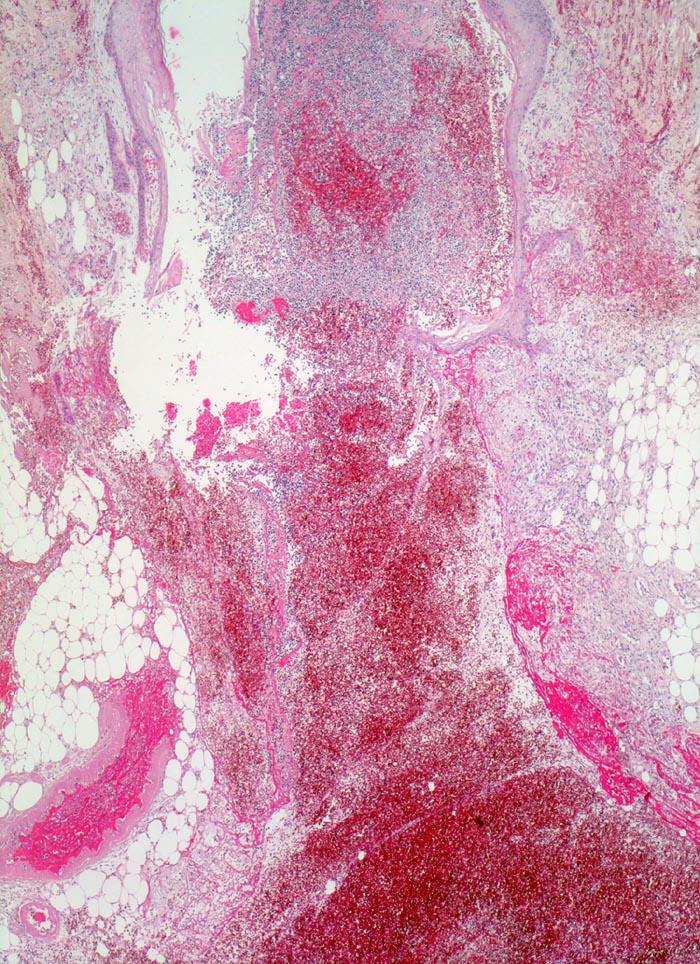

• Schlitzförmiger, bis in die Subkutis reichender Hautdefekt.

• Neugebildete Epidermis bedeckt im oberen intradermalen Anteil des Wundspaltes teilweise den Gewebsdefekt.

• Daran angrenzender Wundspalt im Bereich des subkutanen Fettgewebes mit Fibrinauflagerungen und ödematösem zellarmem Granulationsgewebe.

• An der Basis des Präparates Auseinanderklaffen des Wundspalts wegen grösserem Blutkoagel (verursacht Wundheilungsstörung).